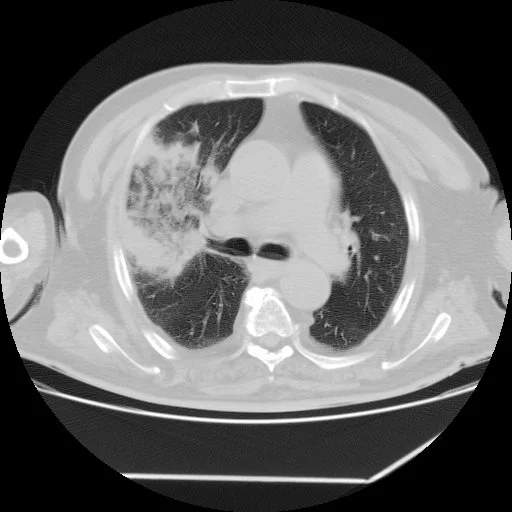

Atoll Sign (Reverse Halo Sign)

• Atoll = circular island with water in the middle (looks like a doughnut)

• Central ground glass opacity with consolidative/enhancing rim

• DDx:

• Cryptogenic organizing pneumonia - main cause

• Fungal pneumonia

• Wegeners (granulomatosis with polyangitis)

• Sarcoid or TB

• Others